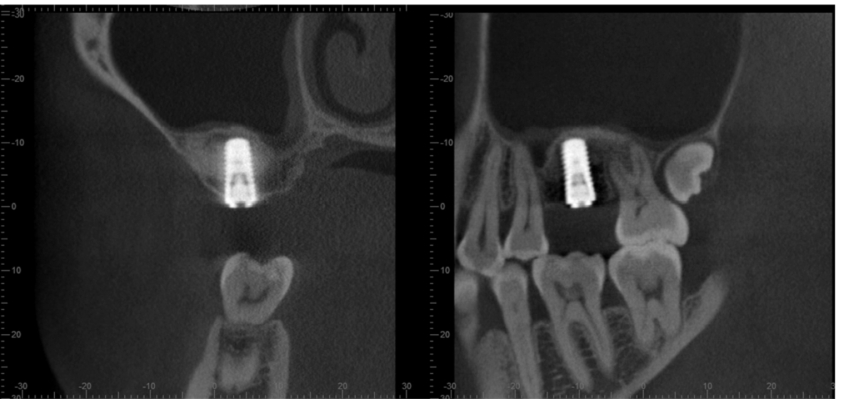

术后当天CBCT,三维方向显示种植体周围及种植体顶部均有充填的骨粉,上颌窦底黏膜完整,提升效果良好(图5)。

图5 术后当天CBCT

术后8个月,CBCT可以在三维方向清楚地显示种植体周围及种植体顶部均有骨组织结合(图6),提示可以完成上部结构修复(图7)。

图6 术后8个月